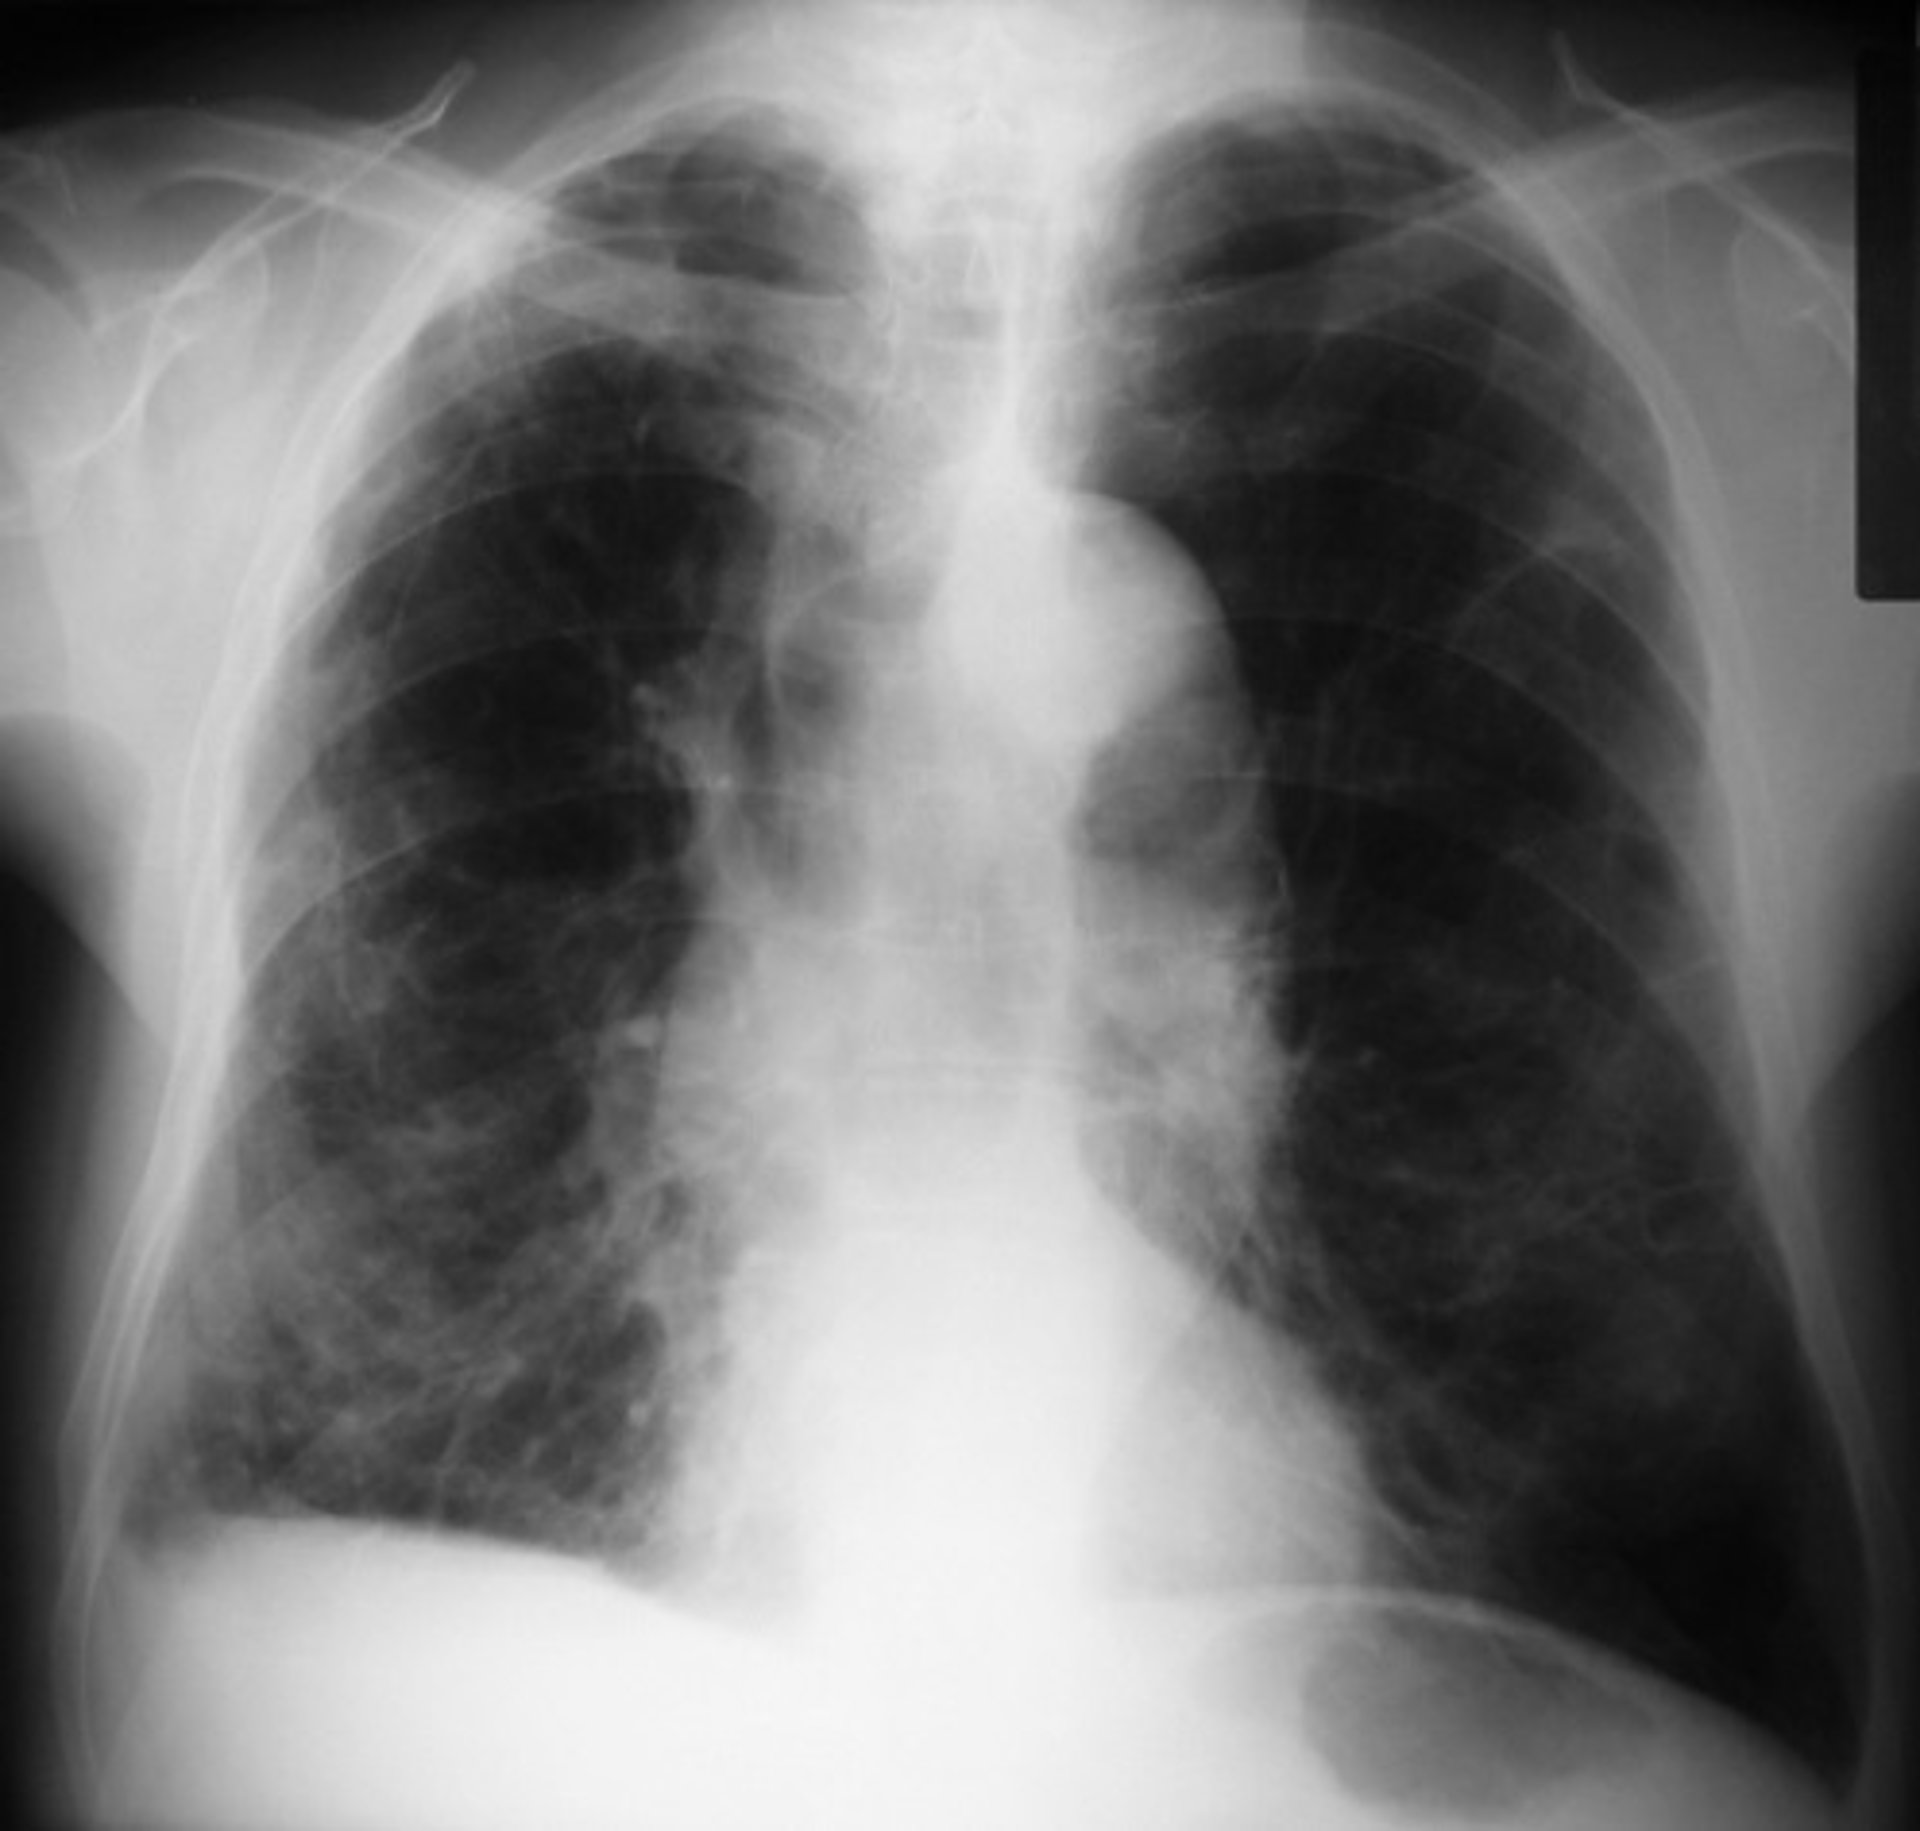

EPOC - FLICKR//PICASA - Archivo

La enfermedad pulmonar obstructiva crónica (EPOC), una afección pulmonar debilitante, a menudo se desarrolla como resultado del tabaquismo, pero los investigadores se han preguntado por qué casi un tercio de los casos ocurren en personas que nunca fumaron. Ahora pueden finalmente tener una respuesta, y puede estar relacionada con el desarrollo de los pulmones en ciertas personas.

La EPOC causa el bloqueo del flujo de aire y problemas relacionados con la respiración que pueden limitar severamente las actividades cotidianas de una persona. El tabaquismo, el asma o la contaminación del aire representan muchos casos de EPOC, pero hasta el 30% de los casos ocurren en personas que nunca fumaron, y solo una minoría de los fumadores empedernidos desarrollan la enfermedad, lo que sugiere que hay otros factores de riesgo en juego.